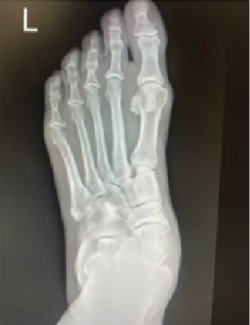

The concept of medial column fixation in Charcot foot utilizes the strength of the multiple screw fixation points and spanning to areas of stronger bone to stabilize the medial column. In our experience, this form of fixation has demonstrated...